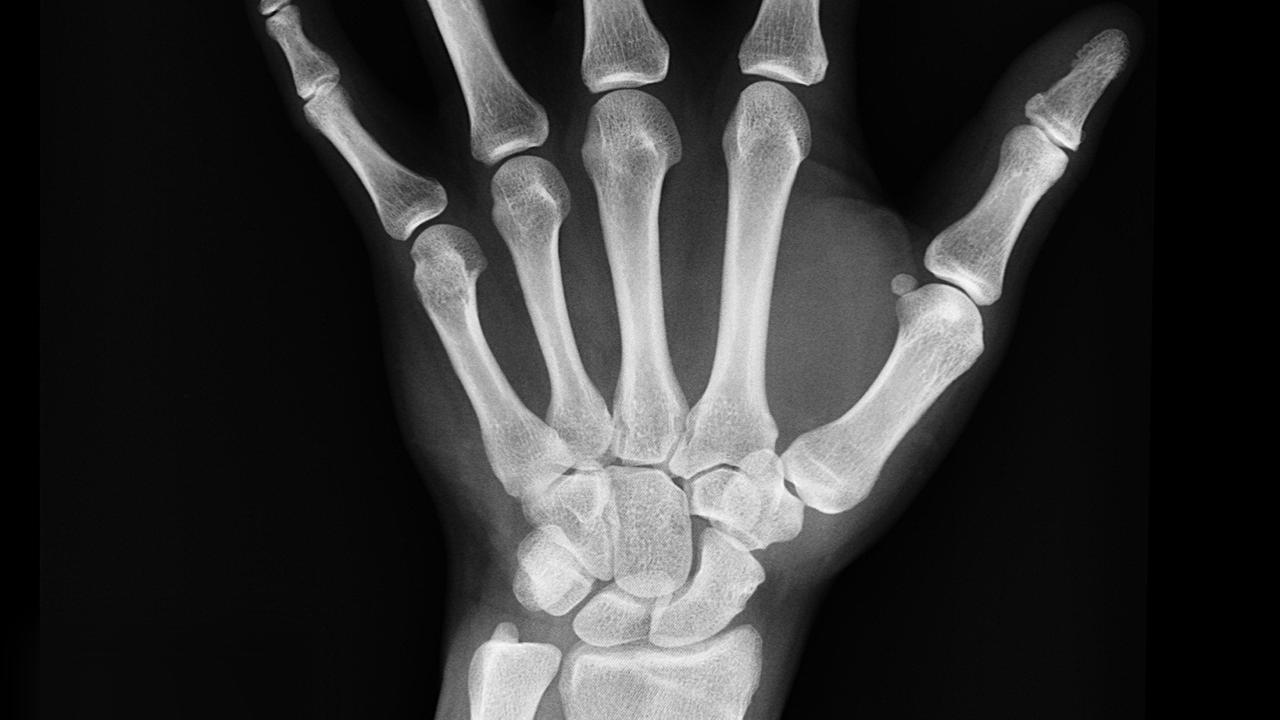

Fungsi tulang telapak tangan tidak lepas dari struktur yang membentuk anatomi tulang telapak tangan. Tulang telapak tangan adalah bagian dari tulang manusia yang terletak di pergelangan tangan dan pangkal jari-jari. struktur atau anatomi tulang telapak tangan mencakup tulang karpus, metakarpus, dan falang, memainkan peran penting dalam mendukung dan memungkinkan gerakan tangan.

Tulang karpus adalah kelompok delapan tulang kecil yang terletak di pergelangan tangan. Mereka terdiri dari dua baris, yakni baris proksimal dan baris distal. Baris proksimal terdiri dari tulang skafoid, lunate, triquetrum, dan pisiform, sementara baris distal terdiri dari tulang trapezium, trapezoid, capitate, dan hamate.

Fungsi tulang karpus adalah menghubungkan tulang panjang lengan bawah (radius dan ulna) dengan tulang metakarpus yang membentang di sepanjang telapak tangan. Ini membentuk kerangka dasar pergelangan tangan dan memungkinkan pergerakan dan fleksibilitas.

Tulang metakarpus adalah kelompok lima tulang yang membentang dari tulang karpus hingga tulang falang dalam jari-jari tangan. Mereka dinomori dari I hingga V, dengan Metakarpus I berada di bawah ibu jari dan seterusnya hingga Metakarpus V yang berada di bawah jari kelingking.

Setiap tulang metakarpus terdiri dari tiga bagian, yaitu basis, tengah, dan kepala. Kepala tulang metakarpus memiliki bentuk bulat dan terletak di telapak tangan, membentuk buku jari.

Fungsi utama tulang metakarpus adalah sebagai jembatan antara tulang karpus dan tulang falang, membentuk kerangka tangan. Mereka juga berperan dalam menjaga keseimbangan dan memungkinkan gerakan dan fleksibilitas pada jari dan tangan.

Tulang falang adalah tulang panjang yang membentuk jari-jari pada tangan. Masing-masing jari (kecuali ibu jari) terdiri dari tiga bagian: falang proksimal, falang tengah, dan falang distal. Ibu jari hanya memiliki falang proksimal dan falang distal.

Fungsi utama tulang falang adalah memberikan kerangka pada jari dan memungkinkan gerakan dan fleksibilitas jari-jari tangan. Mereka memungkinkan kita untuk meraih, menggenggam, dan melakukan berbagai aktivitas sehari-hari.

Seluruh rangka tangan, termasuk tulang karpus, metakarpus, dan tulang falang, bekerja sama untuk memberikan fleksibilitas dan dukungan saat kita menggunakan tangan dalam berbagai aktivitas. Pemahaman tentang anatomi dan fungsi ini penting dalam pengobatan cedera, diagnosa gangguan, dan perawatan tangan secara umum.